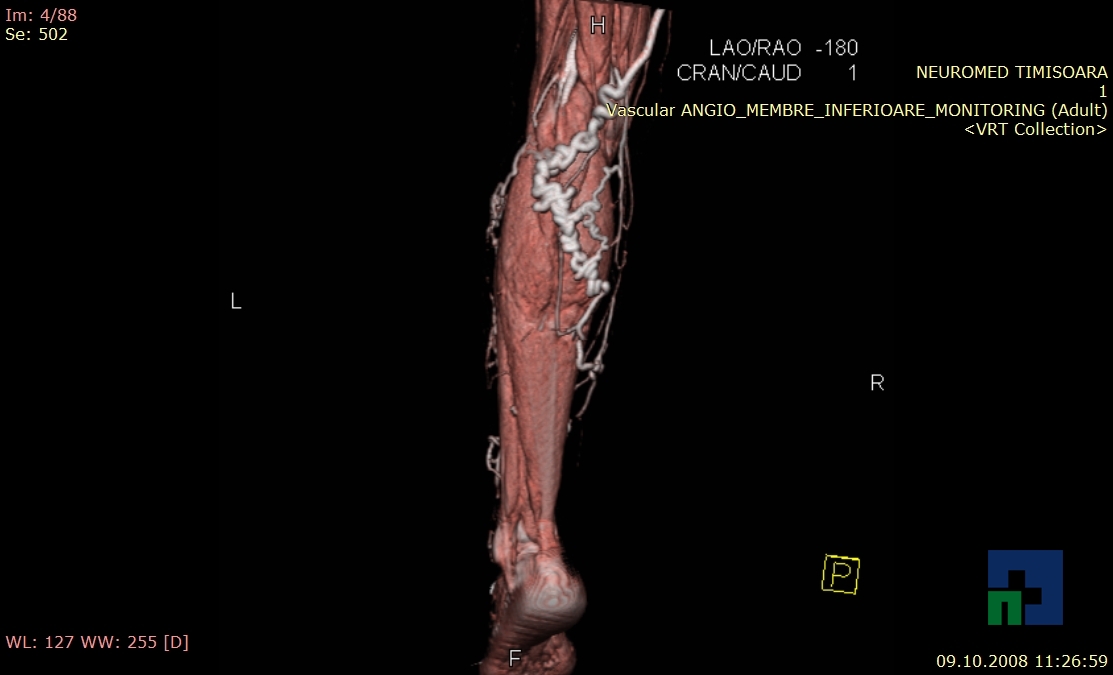

Examinare de rutină cerebrală, nativ și cu substanță de contrast (SDC) pentru diagnosticul:

- Fistula carotido-cavernoasa